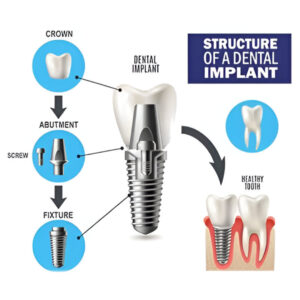

What Are Dental Implants?

A dental implant is an artificial tooth root placed inside the jawbone to support a replacement tooth. It is usually made from titanium, a strong and body-friendly metal. After placement, the implant slowly joins with the jawbone and becomes very stable. A crown (artificial tooth) is fixed on top, giving a natural look and strong bite.

Main Parts of a Dental Implant

Implant has three simple parts:

Implant Screw – Placed inside the jawbone and acts like a tooth root.

Abutment – Connects the implant to the artificial tooth.

Crown –The visible tooth that matches your natural teeth in color and shape. When placed by an experienced implantologist, implants stay strong and comfortable for many years.